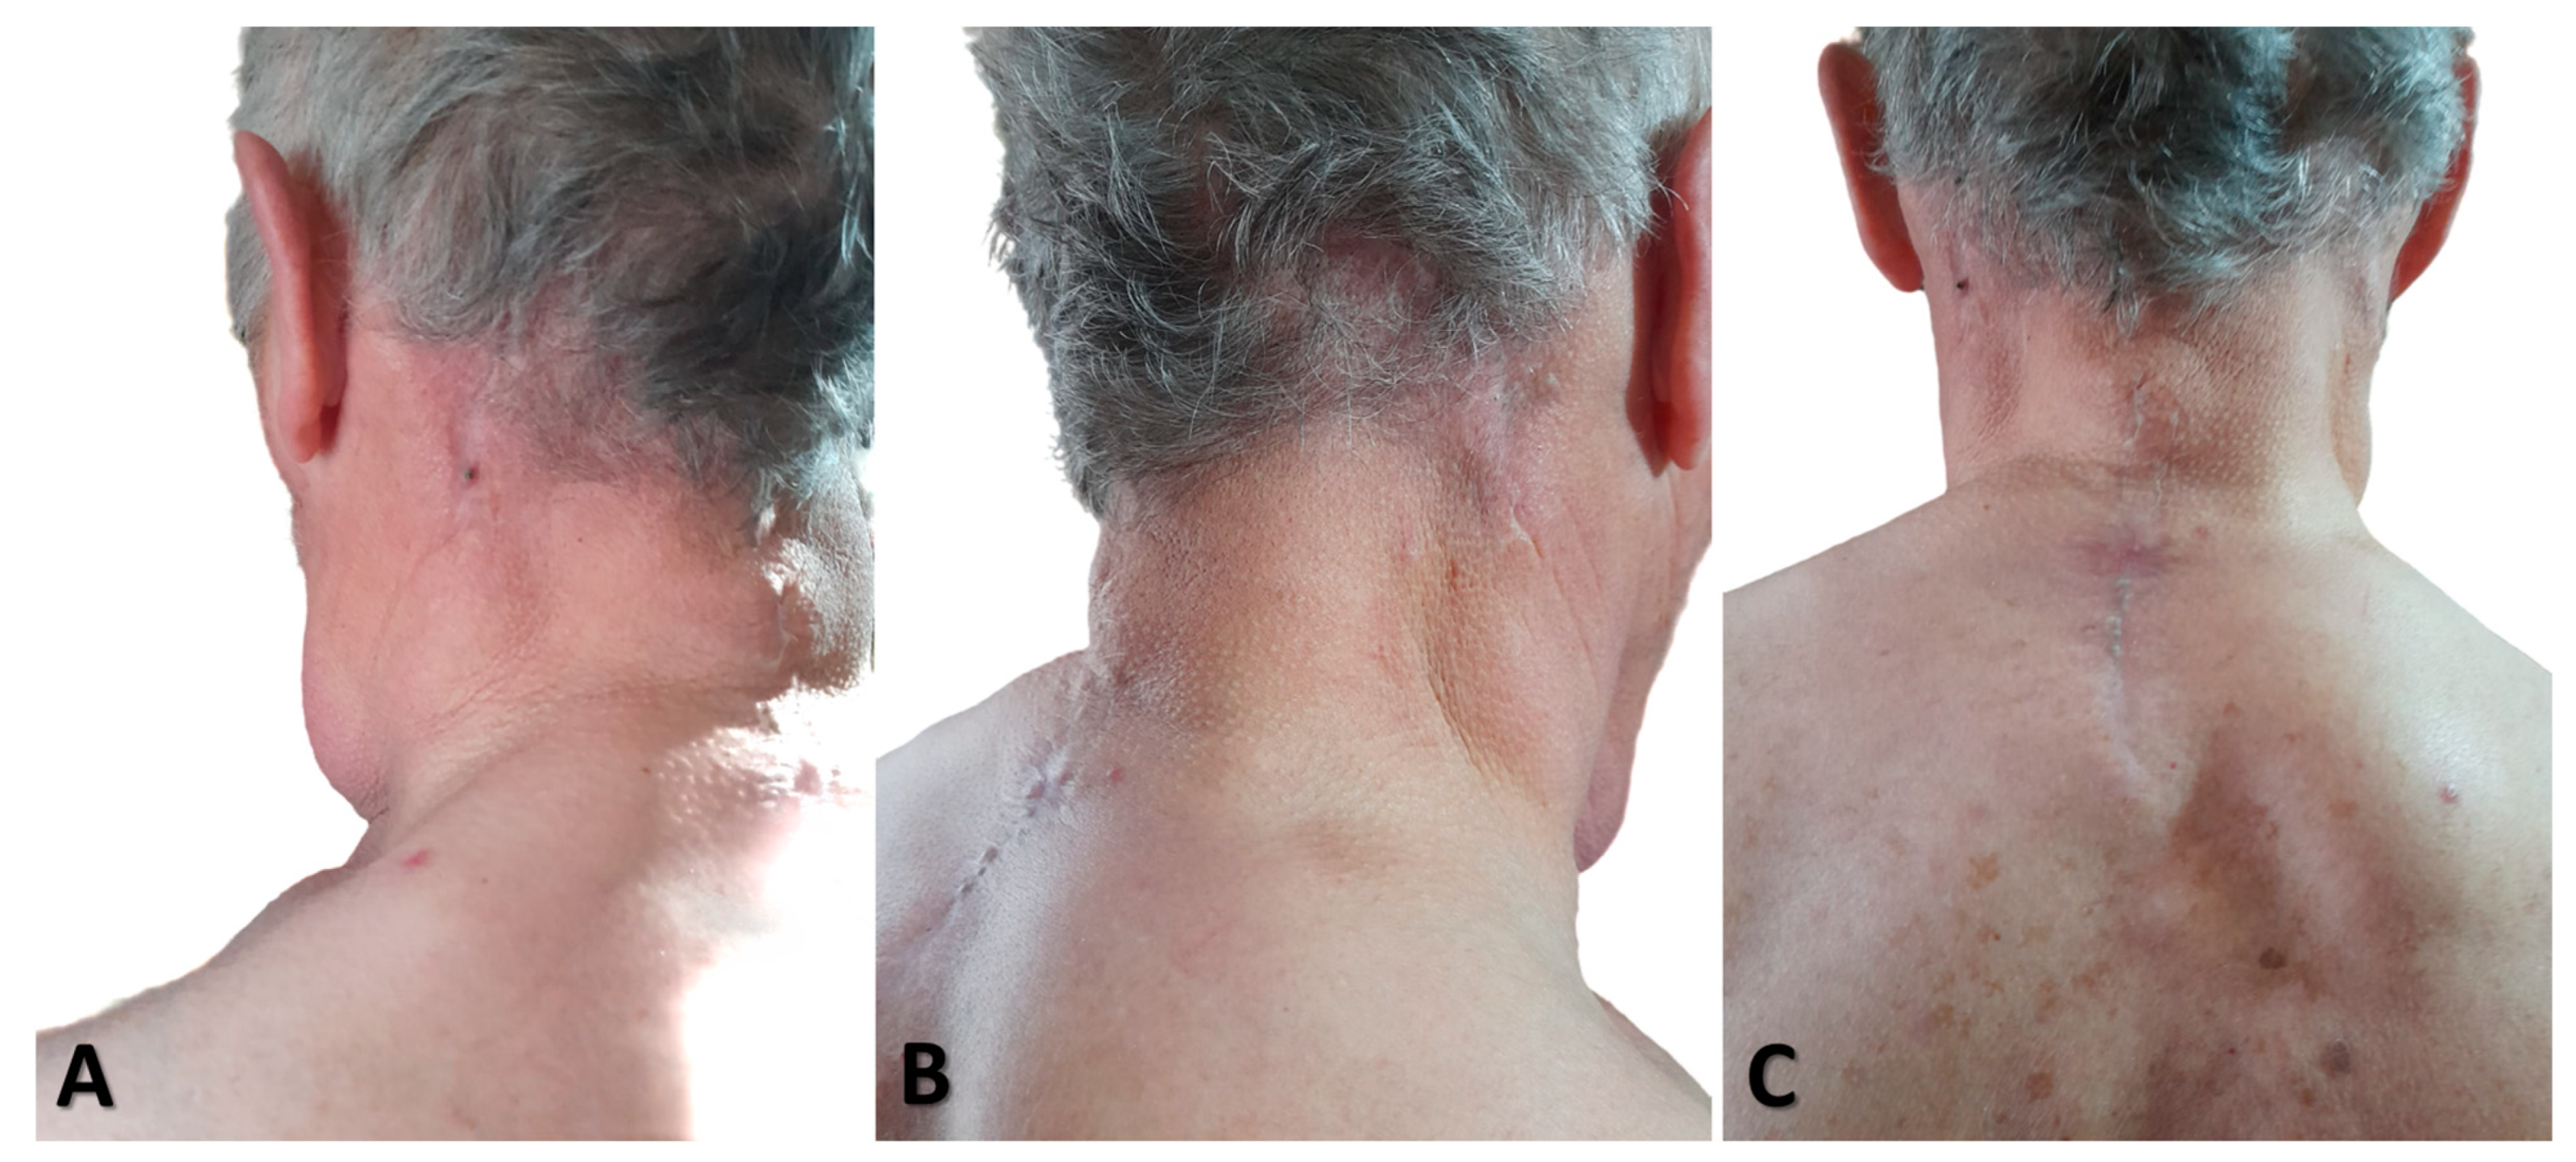

2.1. Clinical Data

2.3. Surgical Treatment